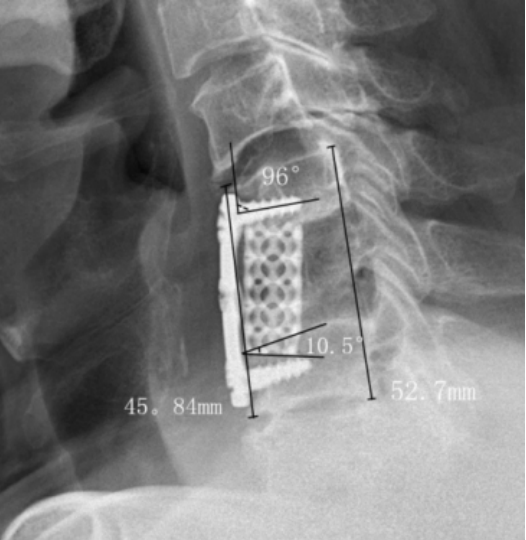

應(yīng)用效果展示: